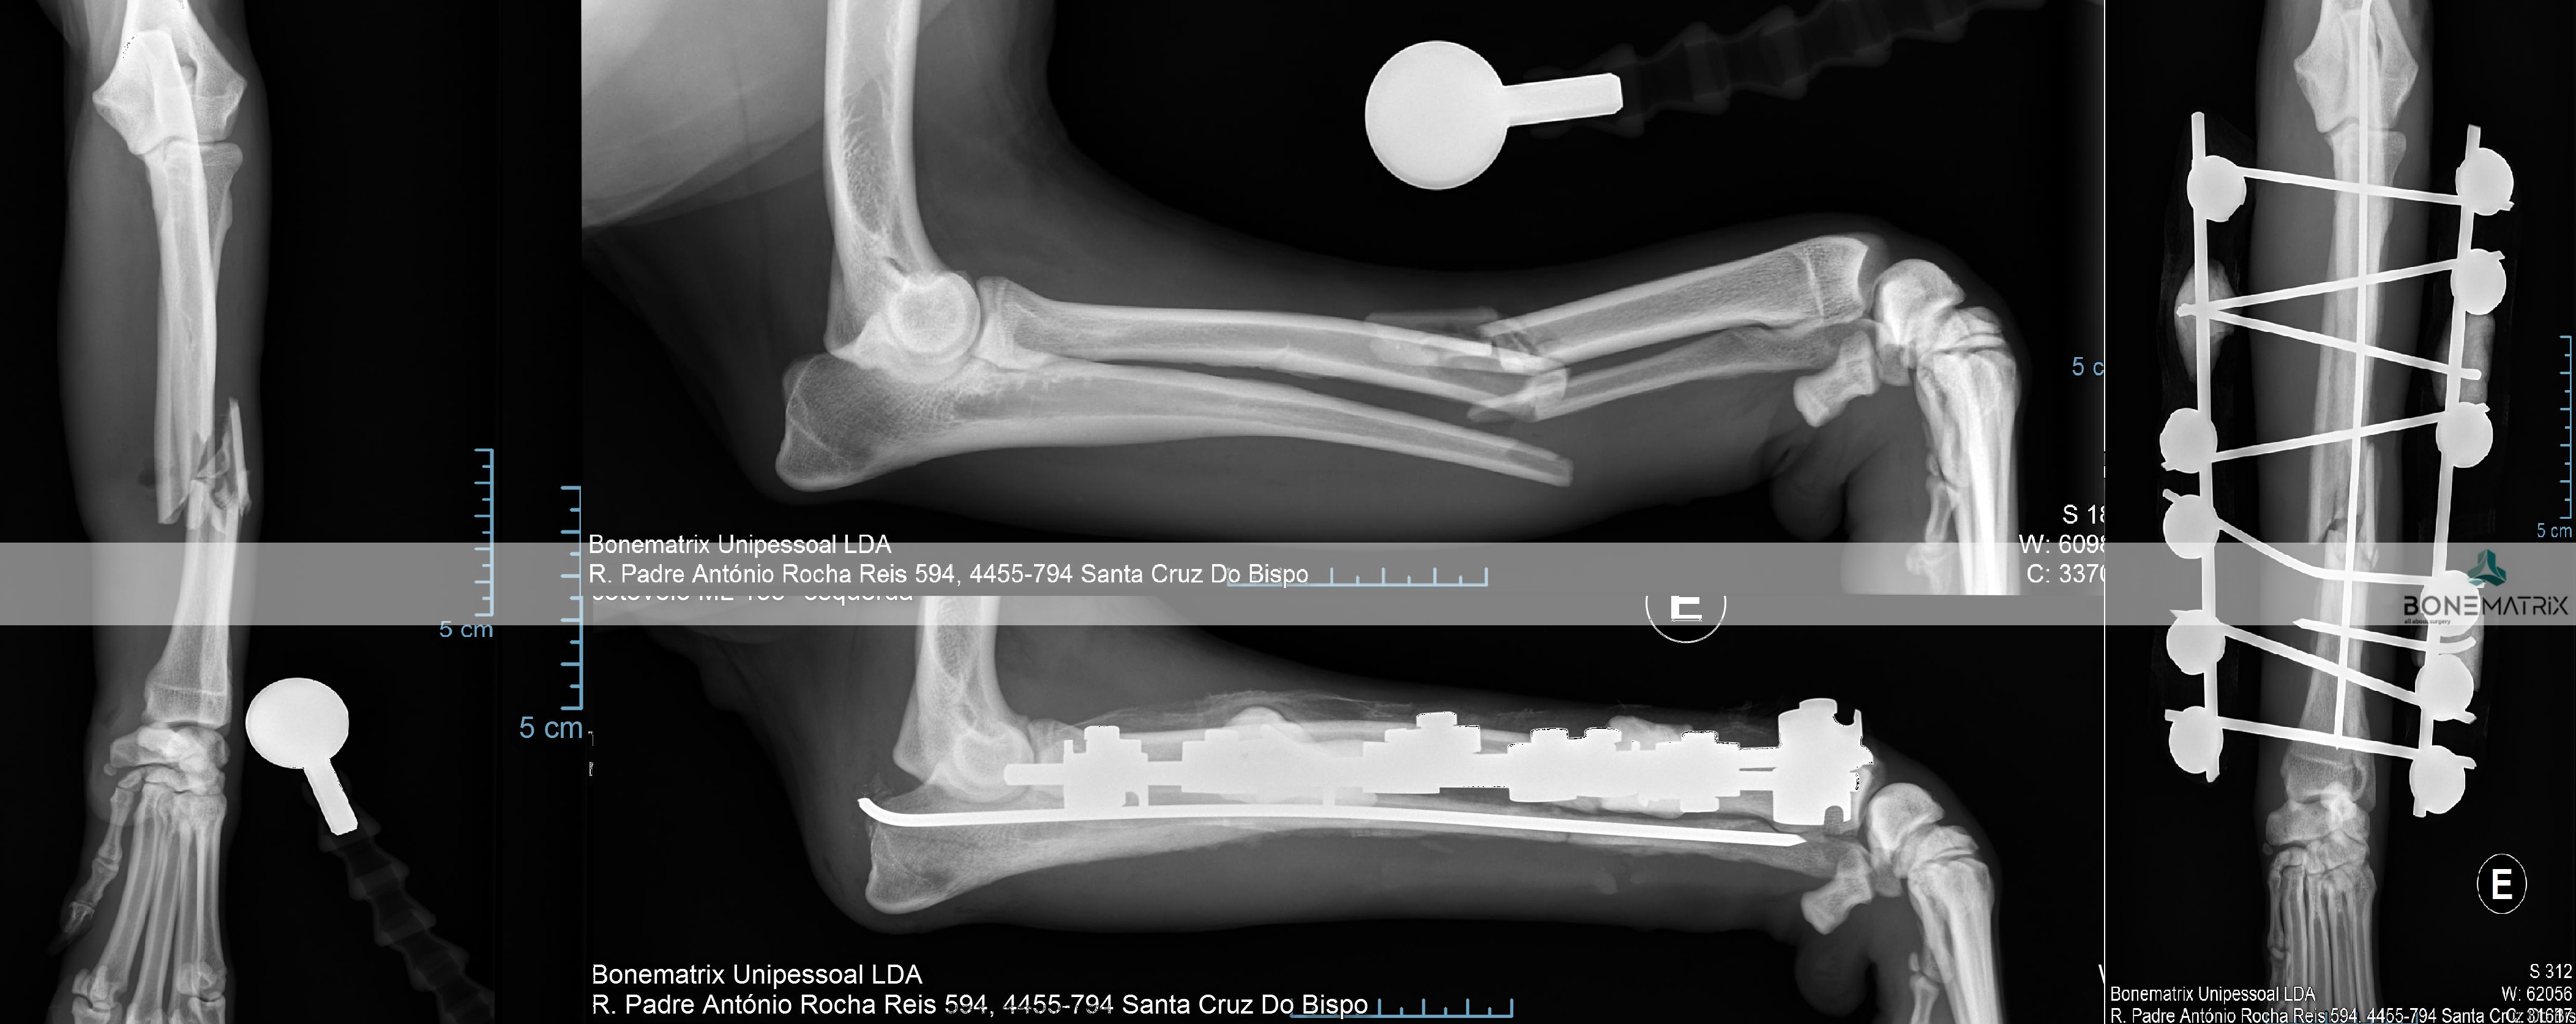

O que é?

A artrodese é uma técnica cirúrgica usada como procedimento de salvage em situações onde não é possível restabelecer a função de uma articulação.

O objetivo desta cirurgia é eliminar a dor articular, estabilizando todos os ossos constituintes da articulação, num ângulo pré-definido. A dor é eliminada pela eliminação do movimento, ou seja, a função articular desaparece e os ossos deixam de se movimentar uns sobre os outros.

A cirurgia consiste na remoção da cartilagem entre os ossos constituintes de uma articulação e colocação de um enxerto ósseo (retirado por norma do ombro do animal) entre os espaços articulares criados. Seguidamente a articulação é estabilizada com recurso a placa e parafusos bloqueados. Por fim o osso irá desenvolver-se entre os espaços onde outrora existia cartilagem e irá, funcionalmente, funcionar como um osso só, eliminando a função articular.

Qual a taxa de sucesso esperada?

A taxa de sucesso desta cirurgia é muito elevada no sentido de cumprimento do objetivo de cirurgia. Outros fatores tem de ser tomados em consideração relativamente ao outcome como resolução cirúrgica, dependendo este da patologia primária.

A PAUL (proximal abducting ulnar osteotomy) é uma técnica cirurgica empregue quando existe doença do compartimento medial.

A cirurgia consiste num corte realizada ao nível do osso da ulna que permite a criação de um deslocamento do osso lateralmente. Esta nova posição do osso é estabilizada com recurso a placas bloqueadas (que conferem elevada segurança ao procedimento) que são especificas para esta cirurgia, conservando a forma do desvio criado pelo corte.

O objetivo desta cirurgia é retirar grande parte do peso do animal, durante o apoio, da região lesionada do cotovelo. Desta forma permitimos que o estimulo ofensivo sobre a articulação deixe de ser exercido sobre esta área e continue a aumentar a lesão.

Este procedimento tem também por objetivo dar conforto ao animal, porque a retirada do peso desta zona, vai permitir um alivio da dor sentida pelo paciente na articulação.

Este procedimento é curativo?

Este procedimento poderá ajudar a tornar o cotovelo mais congruente e desta forma resolver parte do problema existente. A cartilagem é um tecido com pouca capacidade regenerativa por isso o facto de retirarmos o estimulo ofensivo da região não irá resultar num retorno deste tecido a um estado saudável apenas cessará o desenvolvimento das lesões.

O meu animal vai desenvolver artrose nesta articulação?

As lesões de osteoartrite desenvolvidas não serão recuperadas por isso quadros de osteoartrite vão manter-se mas terão um desenvolvimento mais lento da patologia pela melhoria da congruência articular.

Esta cirurgia apresenta alta taxa de sucesso no sentido da retirada de peso do compartimento medial da articulação. Apesar da melhoria evidente na maioria dos casos, também é comum que a recuperação do conforto articular não seja de 100% devido às lesões concorrentes existentes na articulação.

Os fixadores externos consiste num método de estabilização de fraturas que por norma evita que seja realizada uma exposição aberta do foco de fratura.

Existem várias configurações que poderão ser realizadas com fixadores externos, variando de acordo com o tipo de fratura e o osso fraturado.

Por norma, nas configurações lineares, são utilizados K-wires e barras para fazer a estabilização externa.

Estes sistemas aplicados vão atravessar o osso em determinados pontos (por meio de K-wires) de forma a conseguir uma estabilização da fratura quando a sua posição é fixada às barras (implante de maior diâmetro que interseta os K-wires perpendicularmente).

As placas de síntese são sistemas de fixação interna aplicados sob o foco de fratura com o intuito de conseguir a estabilização necessária para que ocorra a cicatrização óssea.

Existem várias placas de síntese dentro dos diferentes sistemas.

Esta técnica envolve a utilização de placas e parafusos para estabilização.

Existem dois sistemas principais de placas que podem ser aplicados em fraturas com diferentes características, o sistema DCP (placa de compressão dinâmica) e o sistema locking (placas bloqueadas).

O sistema locking é um sistema muito mais versátil, capaz de conseguir a mesma segurança na estabilização, de qualquer caso onde possa ser aplicado uma placa DCP. Já o contrário não se passa. Existem fraturas que pelas suas características é aconselhada a preferência por uma placa locking, por apresentarem uma segurança superior.

As placas também podem ser características da correção de fraturas em determinados locais, ou poderão ser especialmente concebidas para a estabilização num único tipo de procedimento cirúrgico.